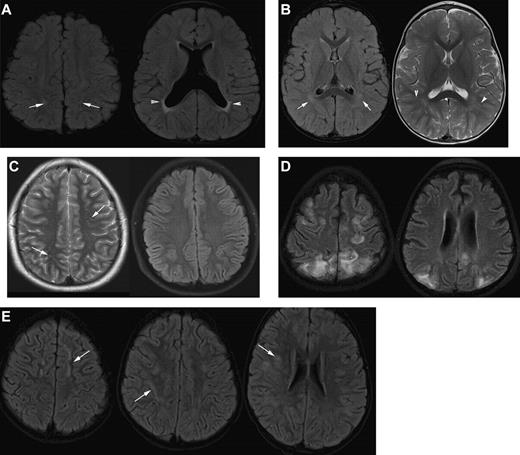

Differential diagnosis of silent infarction (images from patients without SCA). (A) Mimics of SCI: periventricular leukomalacia (PVL). A 20-month-old boy with cerebral palsy characterized by spastic diplegia. Axial FLAIR MR images illustrate classic findings of PVL. The image on the left is at the level of the centrum semiovale and demonstrates bilateral hyperintensities in the parietal lobe white matter. This appearance of the white matter overlaps with the presentation of SCI. The image on the right at the level of the basal ganglia illustrates dysmorphic lateral ventricles, thinning of the periventricular white matter and periventricular signal hyperintensity in a predominantly posterior distribution. Taken together, the images are consistent with the diagnosis of PVL in the setting of prematurity and cerebral palsy rather than SCI. (B) Terminal zones of myelination. A 2-year-old boy with a normal MRI of the brain. The Axial FLAIR MR image (left) shows ill-defined hyperintensity bilaterally in the deep white matter adjacent to the atria of the lateral ventricles (arrows). The T2-weighted image on the right illustrates that there are well-defined linear perivascular spaces (arrowheads) traversing the area of vague hyperintensity. This combination of findings is classic for the terminal zones of myelination, the last areas of the deep white matter to myelinate and displace free water. The terminal zones of myelination remain prominent through the second year of life and become progressively less conspicuous over time. They may be visible into the middle of the first decade of life. (C) Virchow-Robin spaces. A 12-year-old boy withT2-weighted (left) and Axial FLAIR (right) MR images with a normal MRI. The T2-weighted images reveal multiple punctuate white matter hyperintensities that suppresses on FLAIR indicating that the hyperintensities are indistinguishable from cerebrospinal fluid. The fluid attenuation feature of the FLAIR image helps to differentiate perivascular (Virchow-Robin) spaces from SCI. The arrows illustrate another feature of perivascular spaces which is that they appear linear when running within the slice. (D) Posterior reversible encephalopathy syndrome (PRES). A 14-year-old girl with altered mental status and seizures. Axial FLAIR MR images demonstrate hyperintensities bilaterally in the subcortical white matter and overlying cortex with predominant subcortical involvement. The distribution of the signal abnormalities is predominantly posterior and peripheral, a typical distribution for PRES. In contradistinction, SCIs favor the deep white matter of the frontal lobes. Nevertheless, clinical context is the key to differentiating PRES from SCIs. This is especially challenging in patients with SCD because they are prone to development of PRES and SCI. (E) Acute disseminated encephalomyelitis (ADEM). A 5-year-old boy with fever and headache. Axial FLAIR MR images demonstrate patchy, bilateral hyperintensities in the white matter of the centrum semiovale and corona radiata (arrows). Although the image on the left could be confused for SCI in the frontal border zone distribution, the middle and right image show subcortical and patchy hyperintensities that would be atypical in location, size, and lesion definition for SCI. The clinical information is the key to distinguishing lesions of ADEM from SCI.

Strict guidelines for radiographic assessment of SCI require the ability to distinguish SCI from acute and chronic mimics of SCI (Figure 4). Because of the possibility of misclassification of a diagnosis of SCI when a new lesion is suspected, a dialogue between the neuroradiologist, neurologist, and hematologist should occur so both the clinical history and differential diagnoses can be carefully considered.